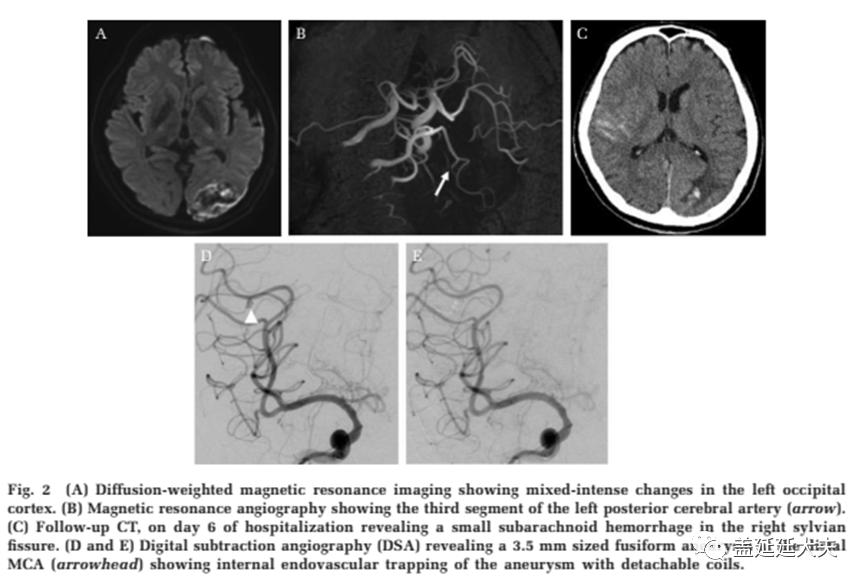

感染性颅内动脉瘤(IIAs) 占所有脑动脉瘤的0.7–5.4% ,被证实继发于症状性的细菌感染,尤其是感染性心内膜炎,偶尔也存在真菌及分歧杆菌的感染。约3-10%的感染性心内膜炎(IE)患者可检查出动脉瘤,远期病情可进展,炎症性栓子脱落导致颅内动脉远端栓塞。对于这些未破裂动脉瘤,采取抗菌治疗可缓解或者缩小其体积。相反地,破裂的,有症状的或正在生长的动脉瘤应该考虑手术或血管内介入治疗。血管内介入治疗变得更受欢迎,并已被采用作为治疗指南。新泻大学神经外科 2002年至2018年就收治的3例IIAs病人进行讨论。包括2男1女,总共6个动脉瘤。平均年龄43.3岁。1例患者最初表现为实质内出血,1例有占位效应,另1例有4个IIAs(1个引起蛛网膜下腔出血(SAH),3个引起迟发性脑实质出血)。所有动脉瘤的直径平均大小为12.2毫米,动脉瘤优先位于大脑后动脉远端以及大脑中动脉。在病例2中, IIA位于大脑中动脉近端。3例为梭状动脉瘤,3例为囊性动脉瘤。所有病例均继发于IE。其中一例致病菌为粪链球菌,一例为唾液链球菌。第三例中的病原体未发现。

5个动脉瘤应用弹簧圈结合NBCA进行栓塞。另1个动脉瘤采用血管内介入结合手术(病例2)。在血管内治疗组,2例使用弹簧圈进行近端血管闭塞,3例使用弹簧圈孤立动脉瘤,1例使用弹簧圈结合NBCA栓塞动脉瘤。除病例2外,所有IIAs均在发现后24小时后治疗。所有患者都有良好的临床结果,无并发症,无动脉瘤复发或再出血。感染性颅内动脉瘤很少见,血管造影上典型的表现是涉及颅内大动脉二、三级分支,多发不规则或梭形的动脉瘤。IIAs通常直径小,但可以迅速扩大。Alawieh等人报告了44.2% IIAs直径<5mm, 少数非典型的病例可出现巨大动脉瘤。56.9%位于MCA, 13.1%位于PCA。我们推测,无症状动脉瘤的动脉内壁可能已经存在一个脓肿,引起炎症和脓囊进展,导致形成巨大的动脉瘤造成占位效应。IIAs可能无法检测到,随着 IE发病至IIA破裂可能持续2 - 5周。感染性心内膜炎(IE)患者必须密切监测一系列神经影像,包括MRA,CTA,特别是发病后2-5周。尽管非侵入性神经成像技术有了进步,但DSA仍然是黄金标准。如果非侵入性检查呈阴性,仍推荐行DSA脑血管造影。

血管内介入治疗作为一种有效的治疗手段正日益受到人们的重视,是IIAs破裂或保守治疗失败的一线方案,包括有着更低的死亡率,更容易接触远端动脉瘤,治疗多发性动脉瘤的成功率更高,对后续心脏手术的延误期更短,相比开颅手术更低的出血风险。特别适用于需要心脏瓣膜置换的感染性心内膜炎(IE)患者。此外,IE患者常伴有心衰,血管内介入是微侵袭手术,对比开颅手术可明显缩短麻醉时间。对于心血管状况不稳定的患者,手术也可以在局部麻醉下进行。所有应用血管内介入治疗IIAs的患者均有良好的临床随访结果,无动脉瘤复发或再出血。临床评估在出血风险高的情况下,动脉瘤的治疗应该尽快进行。血管内栓塞材料可使用弹簧圈结合液体栓塞剂(NBCA,Onyx,以及其他)。Ding曾报道用支架辅助弹簧圈栓塞IIAs。血管内栓塞材料引入受感染者体内血管可引起感染或脓肿的周期延长,然而目前并没有报道表明因此导致延迟或新发的感染并发症。适当的抗生素在围手术期应用可预防感染并发症。